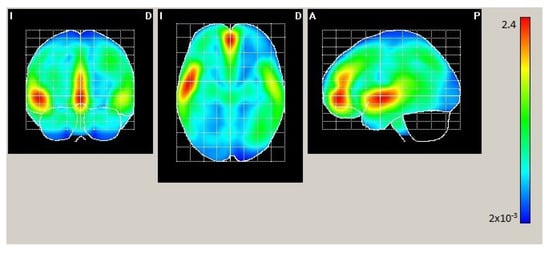

| AAL | X | Y | Z | Act. [µA/m] |

|---|---|---|---|---|

| Frontal_Mid_Orb_L | −2 | 50 | −4 | 2.407 |

| Temporal_Sup_L | −50 | −2 | −4 | 2.401 |

| Frontal_Mid_Orb_R | 2 | 50 | −4 | 2.39 |

| Cingulum_Ant_L | −2 | 50 | 0 | 2.382 |

| Frontal_Sup_Medial_R | 2 | 50 | 0 | 2.364 |

| Frontal_Sup_Medial_L | −2 | 54 | 0 | 2.352 |

| Temporal_Pole_Sup_L | −50 | 6 | 0 | 2.254 |

| Insula_L | −46 | 6 | −4 | 2.249 |